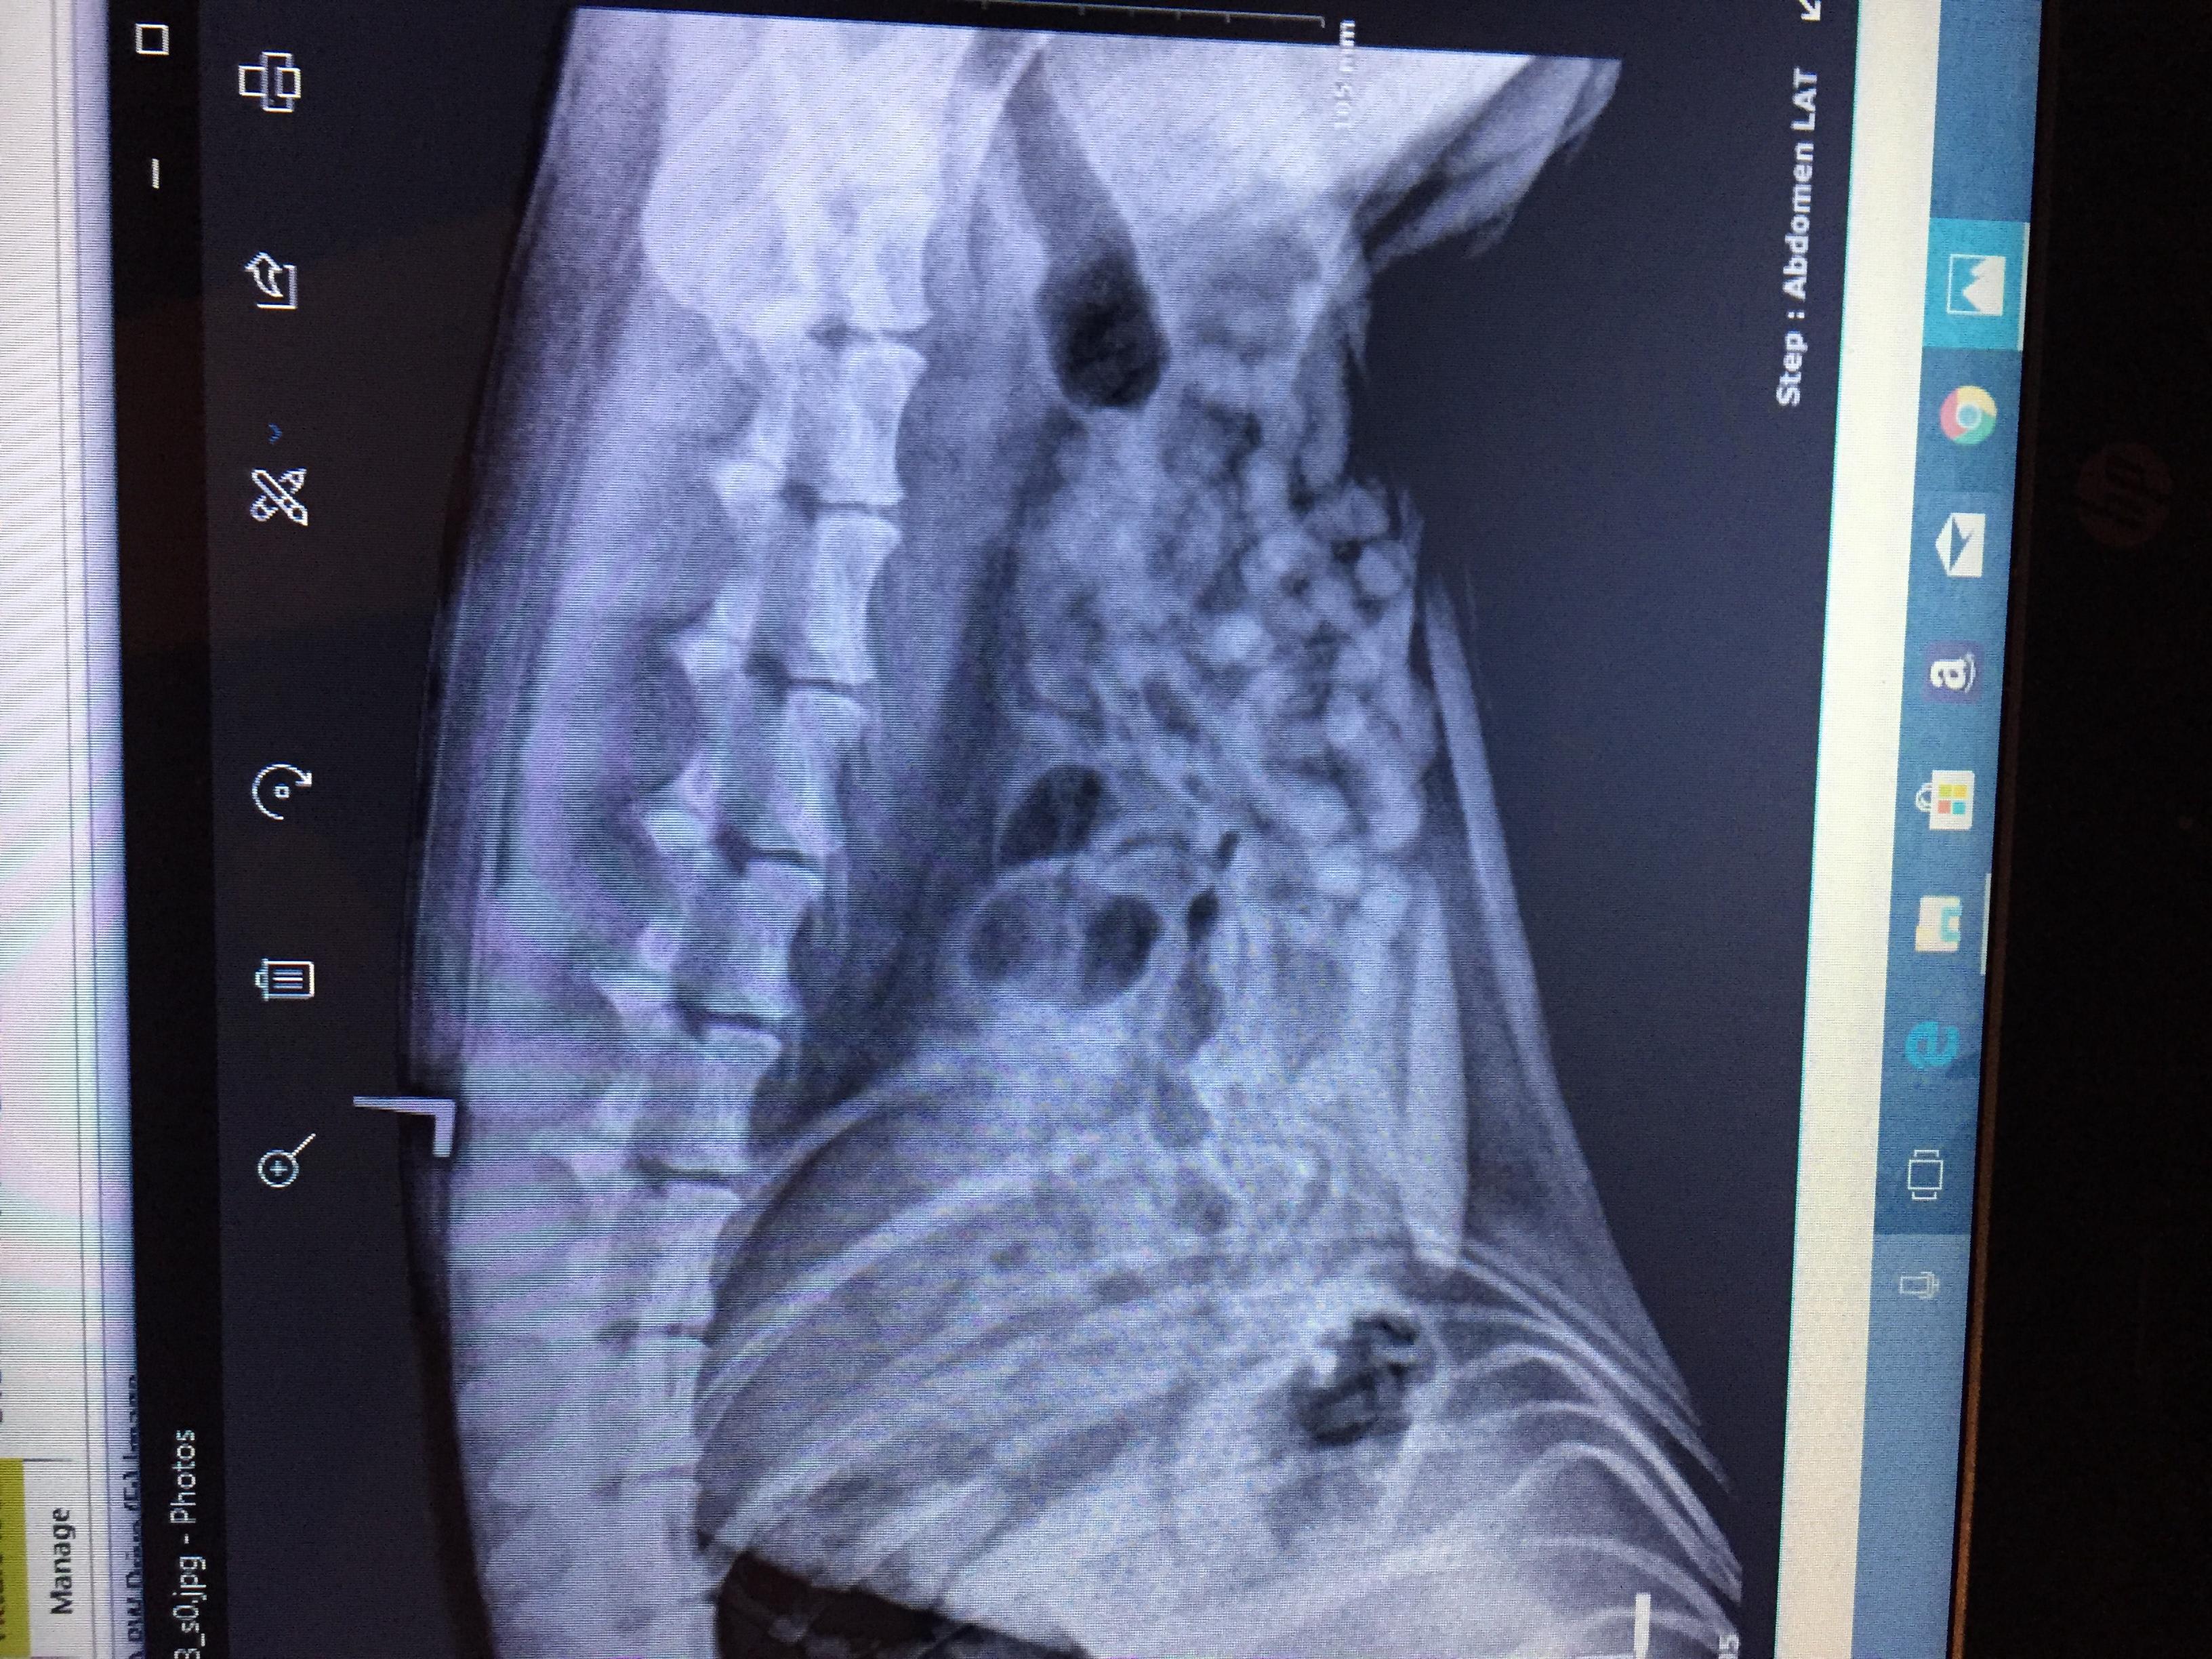

My was recently diagnosed with intestinal parasites called hook worm. the vets also did an X-ray and showed a little concern to a small area where her intestines look bunched up, they asked if she swallows things and I said she likes to eat her toys but always poops them out and I make sure of that. They didn't know what could be causing what they saw on the X-ray since it wasn't really big or obvious, my question is if these intestine parasites can do that to the intestines?

Typically, no, hookworms will not cause the intensities to become bunched. There are some parasites, specifically whipworms, that can cause an intusseception (where the bowel folds in on itself) but this usually causes severe illness (vomiting and diarrhea). Based on the X-rays, it does not look like your dog has any sort of intestinal blockage. If your dog is vomiting or having diarrhea for more than 24-48 hours after being treated for worms, then she will need to be checked out again by your vet. I hope this helps. Thanks for using Petco Pet Education Center, formerly Petcoach. Best of luck!